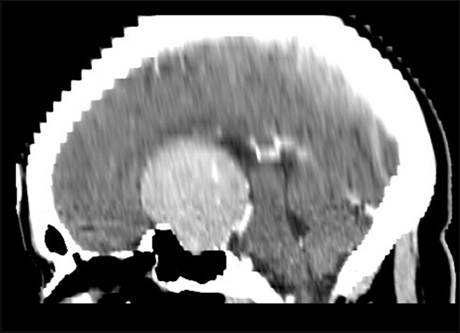

Cerebral Aspergilloma Mimicking Tumoral Mass: A Diagnostic Dilemma

Dr. Jyoti Valecha, Vivek Gupta, Nitin Garg (Author)

87-90